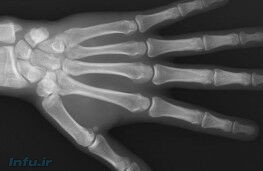

در تحقیقات آنها ابتدا تصویربرداری کاملی از شکستن قلنج مفاصل انجامشده و در ادامه با استفاده از شبیهسازی کامپیوتری، این فرایند بهصورت موبهمو بررسی شد. نتایج به دست آمده نشان از آن داشت که این صدا بهواسطه شکستن حبابهای موجود در مایع سینوویال موجود در مفاصل متاکاراپوپالانژ به وجود میآید.